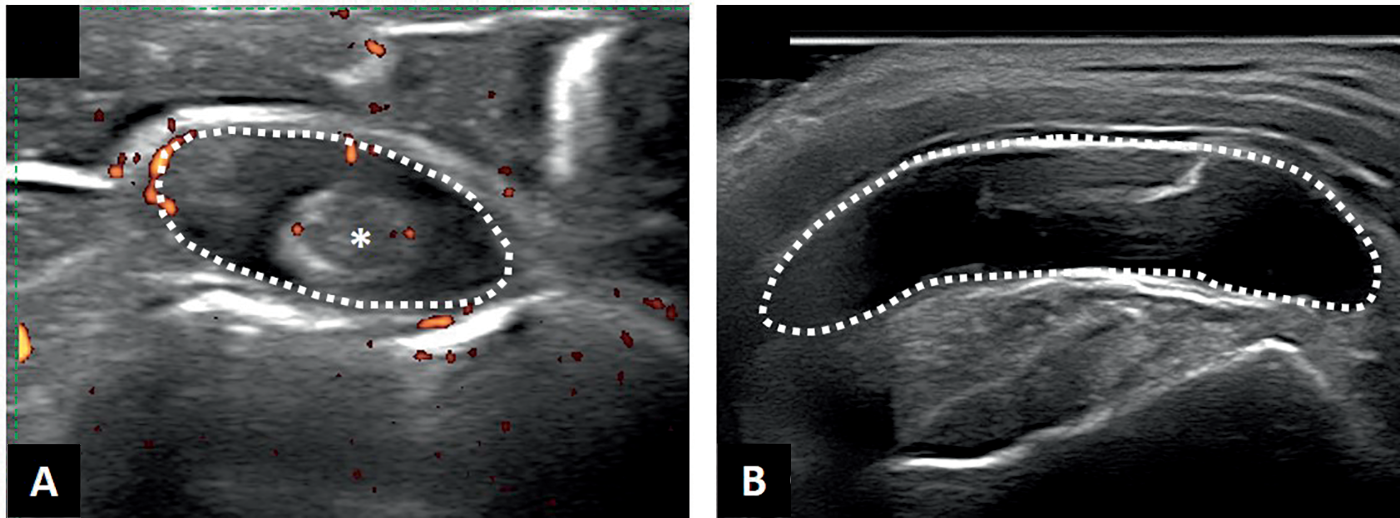

Fig. 16.3.

Échographie dans la pseudopolyarthrite rhizomélique.

A. Coupe transversale du long biceps (*) montrant une ténosynovite (tirets). B. Bursite sub-acromio-deltoïdienne (tirets).

Elle peut révéler (fig. 16.3) :

Dans la mesure où ces anomalies morphologiques sont isolément fréquentes chez le su- jet avançant en âge, c’est surtout le caractère bilatéral et inflammatoire (mode doppler) de ces anomalies qui oriente vers une PPR.